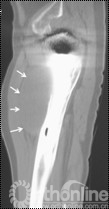

4例因发现腹股沟、或髂窝处渐大、隐痛不适包块而就诊;1例因大腿上外侧出现渐增大无痛性包块就诊;2例术后定期随访拍片发现假体周围局灶性骨溶解,进一步行三维CT扫面发现骨盆内炎性假瘤。所有患者X线片拍片均发现假体周围局灶性骨溶解,假体稳定固定。7例X线发现髋臼DeLee和Charnley II区骨溶解,1例同时伴有股骨侧外侧骨溶解(Gruen II区)。7例三维CT扫描均提示骨溶解区,其中6例CT提示骨盆内软组织包块,1例CT显示大腿前外侧软组织包快(图1)。

图1 CT片示股骨上段GruenII区骨溶解,外侧炎性假瘤形成(箭头所示)